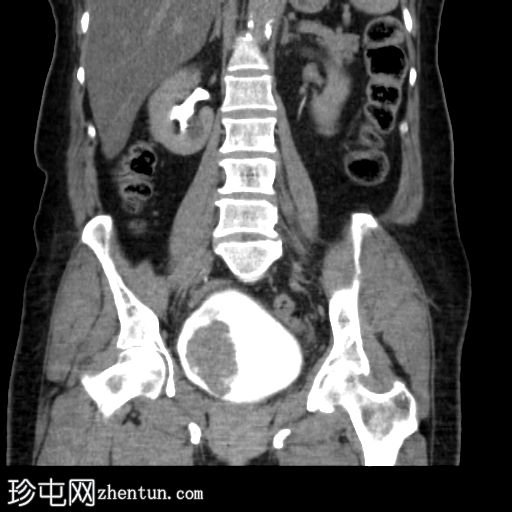

俯卧位轴位扫描

延迟期

4.jpg

冠状位增强扫描

5.jpg

膀胱内可见一边界清晰、不规则、可移动的软组织病变(CT值65 HU),直径约40 mm。病变无钙化,增强扫描后无强化。首要鉴别诊断为血肿。

采用俯卧位CT扫描显示病变活动度。

膀胱镜检查证实存在血肿,并进行了血块清除术。

膀胱血肿常被误诊肿瘤性肿块。俯卧位是区分可移动血块和固定于膀胱壁的肿瘤的关键操作。这种简便的技术,结合无对比剂增强,可提供强有力的非侵入性证据,排除肿瘤性病变。